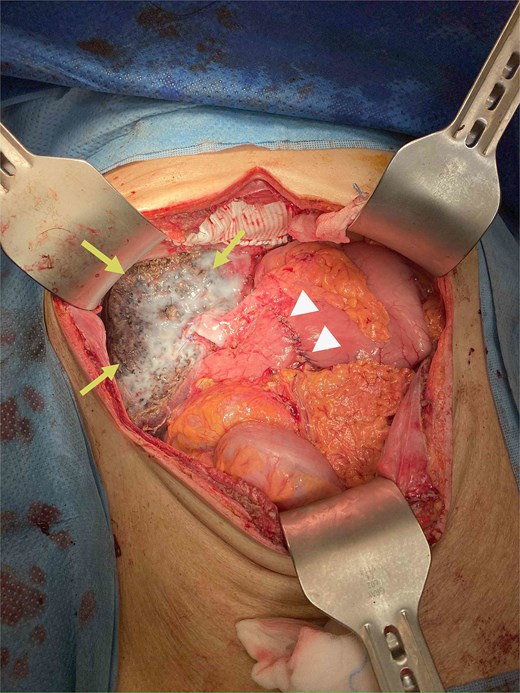

During operation, an exophytic 7 cm segment 4 tumor was found invading superiorly to left hemidiaphragm and pericardium, inferiorly invading to first part of duodenum. A cuff of duodenal wall was removed with tumor and the duodenal defect was closed primarily with 3/0 PDS. Part of the left hemidiaphragm together with pericardium was resected, the heart and left lung were exposed (Fig. 3). The diaphragmatic/pericardial defect was closed with Gore-Tex mesh with single layer continuous 3/0 Prolene (Fig. 4). Air was expelled through an under-water seal catheter placed in the pleural cavity before suture was tightened and tied. Left trisectionectomy was then completed (Fig. 5). The patient developed intra-abdominal collection after surgery which resolved with percutaneous drainage. Pathology confirmed a 7 cm ICC, there was evidence of rupture with abscess formation, and adhesion but no direct invasion to duodenum and diaphragm (Fig. 6). The resection margin was clear. No satellite lesion or microvascular invasion. CEA decreased to normal level after surgery. The patient declined adjuvant chemotherapy.

Operative photo showing the pericardium was removed en bloc with liver tumor, the heart was exposed (arrows).

The diaphragm and pericardium was closed with Gore-Tex mesh (arrows).

Specimen removed, the transected liver surface was covered with applied tissue glue (arrows) and the duodenal repair site was seen (arrow heads).